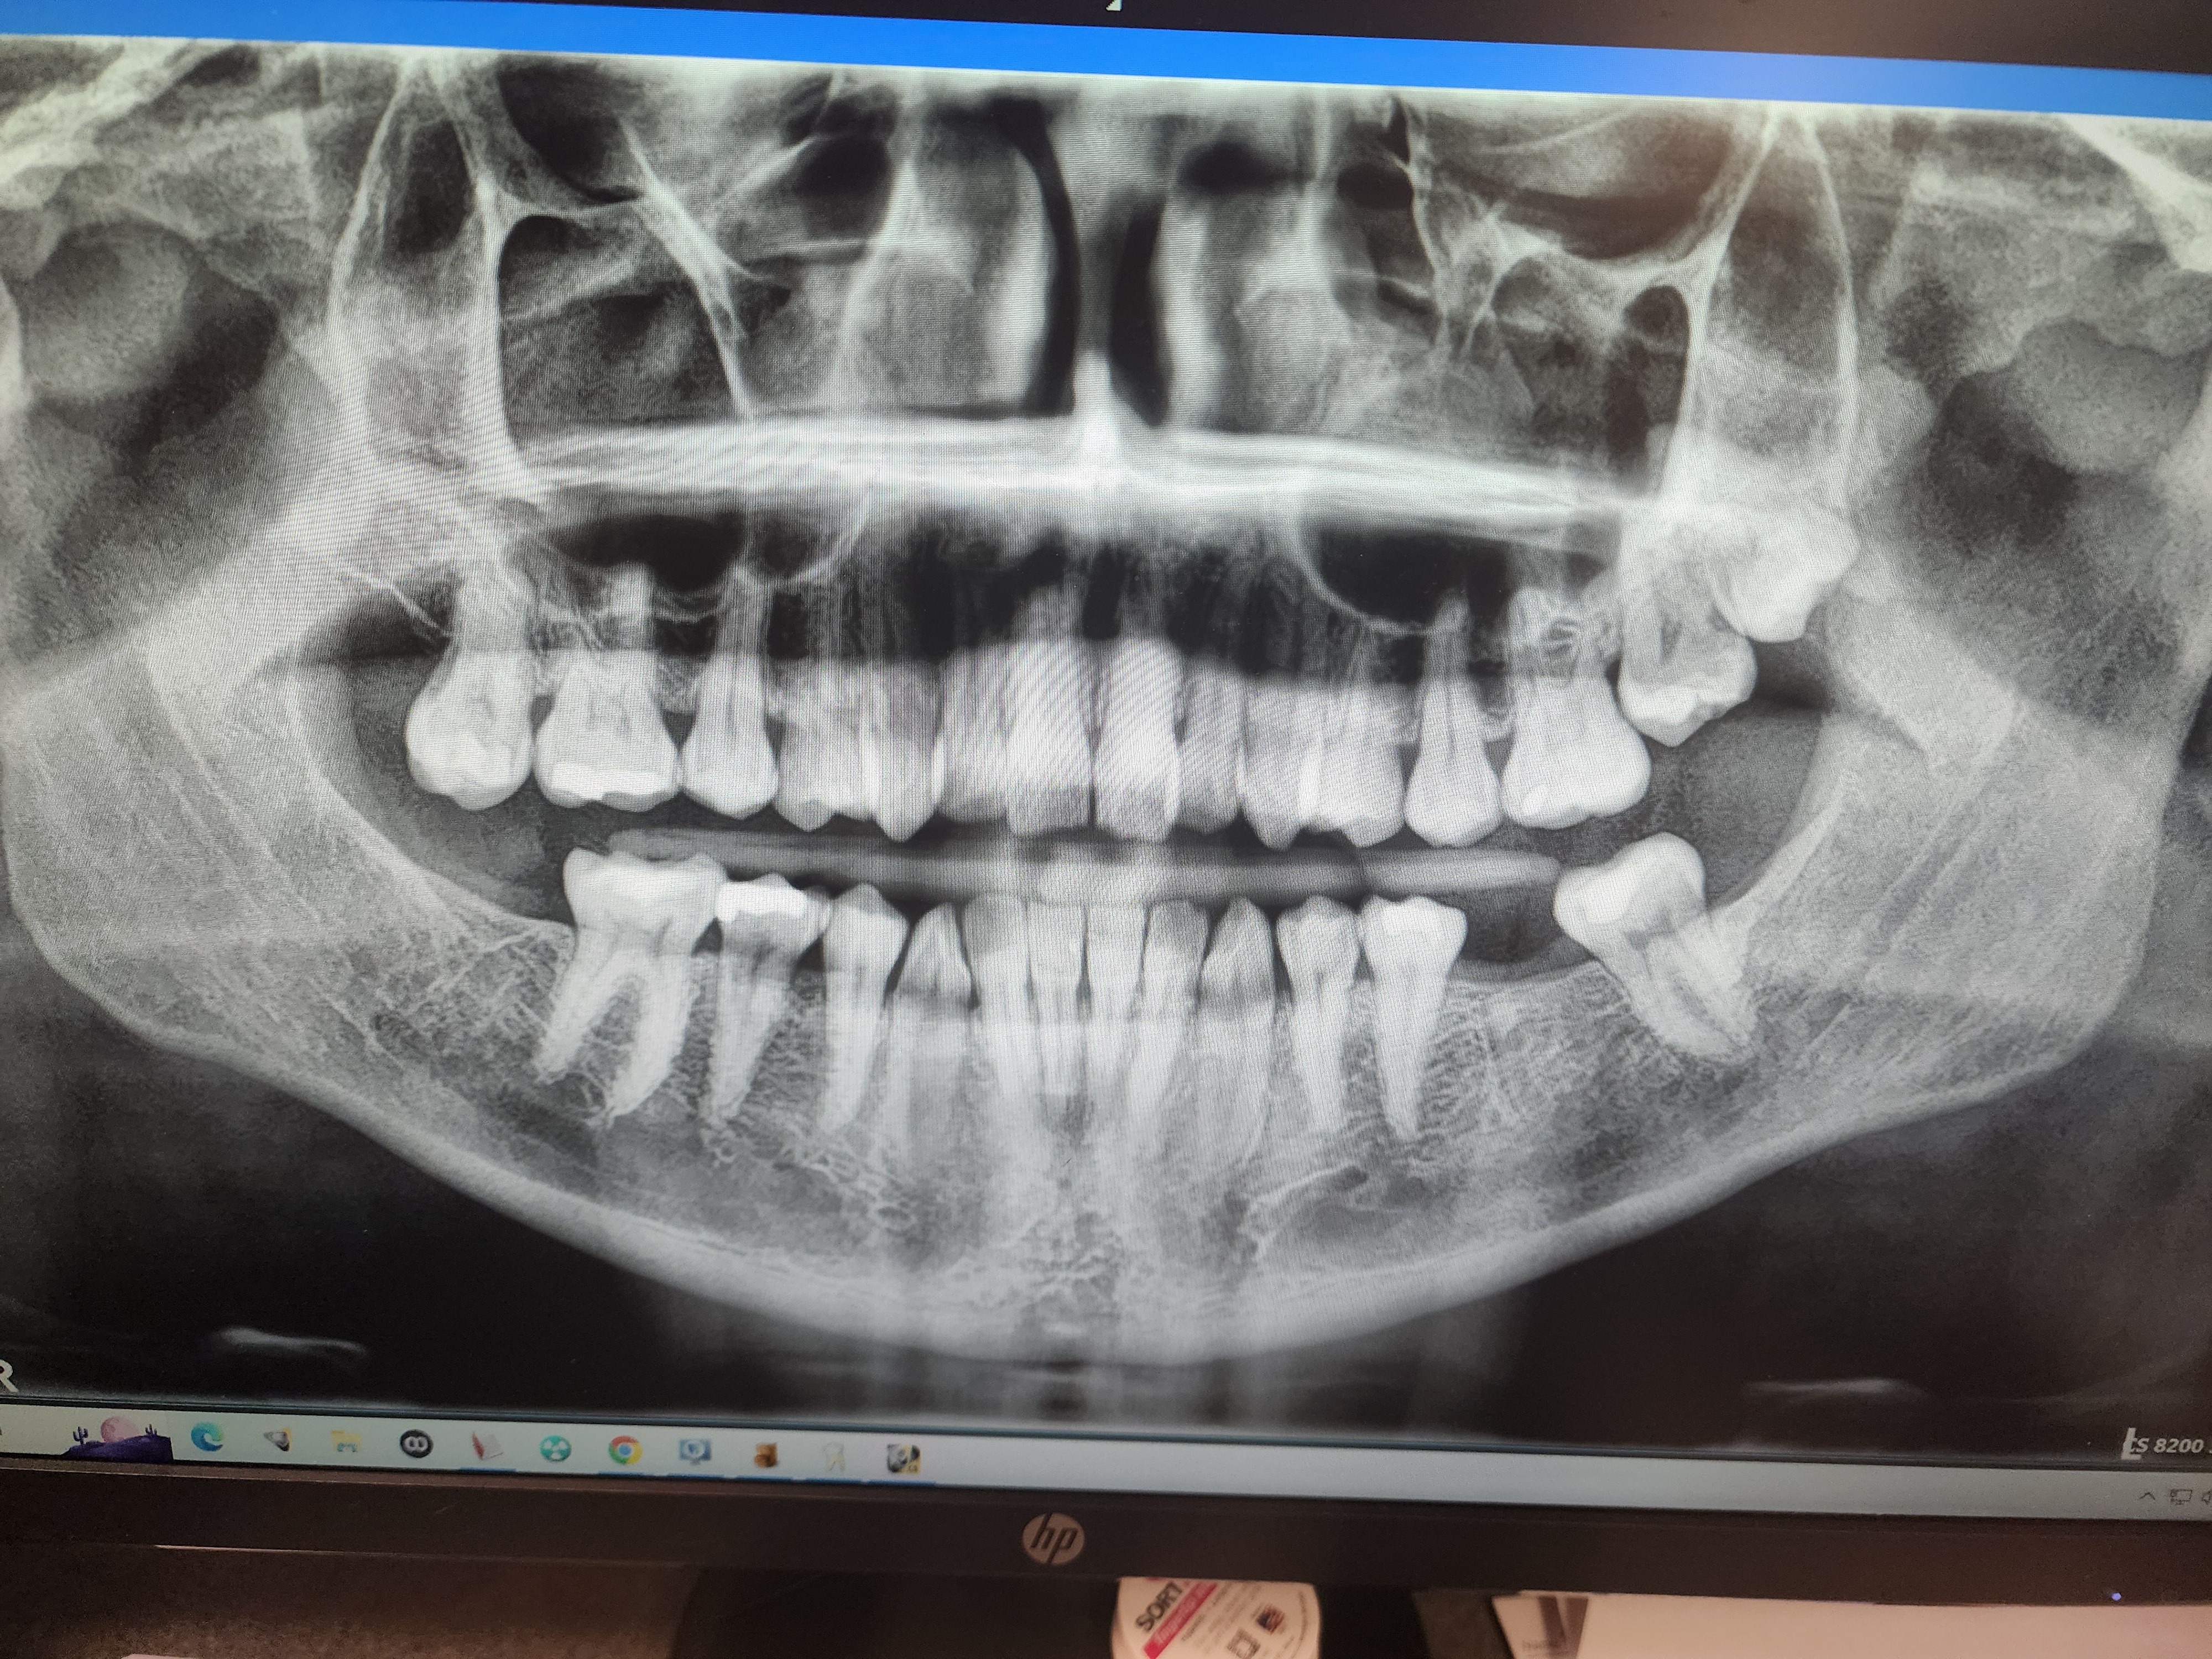

I am trying to raise money for an extremely complicated, but urgent dental surgery to remove an impacted wisdom tooth from my jaw. Unfortunately, I was not blessed with the greatest teeth.

My upper left was left untouched by previous surgeons, insisting that it wouldn't cause any issues. Here I am, 10 years later, with a hairline fracture in my jaw because there is nowhere for it to go. Sounds fun, right? The new surgeon is giving me a significant discount due to being on medicaid, but it still leaves a significant amount of nearly $3000 that I just do not have, which is a big part of why I've been putting this off. Unfortunately, it cannot be delayed any longer.